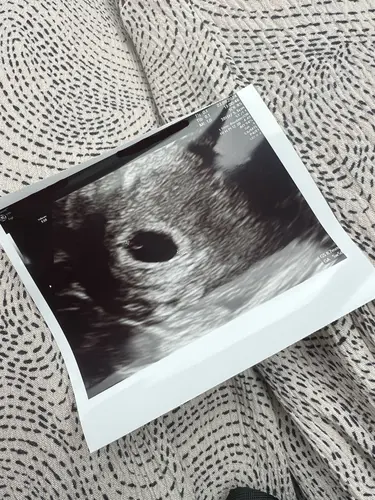

Gaaf ik lees dat veel van jullie al voor de 6e week een kloppend hartje heb ...

Jaahoor! Twee keer gehad nu

Ik lees bijna overal dat dit vanaf 5+3/4 een beetje gebeurt en afhankelijk van hoe goed ze kunnen zien, zou je rond de 6 weken wel een beetje wat moeten kunnen zien ♡